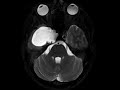

Chondrosarcoma

There is T2 hyperintense, heterogeneously enhancing mass centered in the right middle cranial fossa with infiltration of the right petrous ridge and encasement of the petrous and cavernous segments of the right internal carotid artery, compatible with a skull base chondrosarcoma. This was confirmed at pathology.